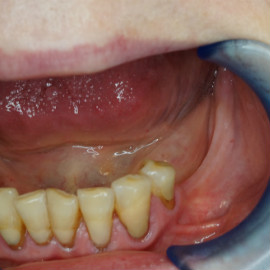

Brakujących pięć zębów dolnych w odcinku wargowym. Rekonstrukcja tkanek i rehabilitacja protetyczna.